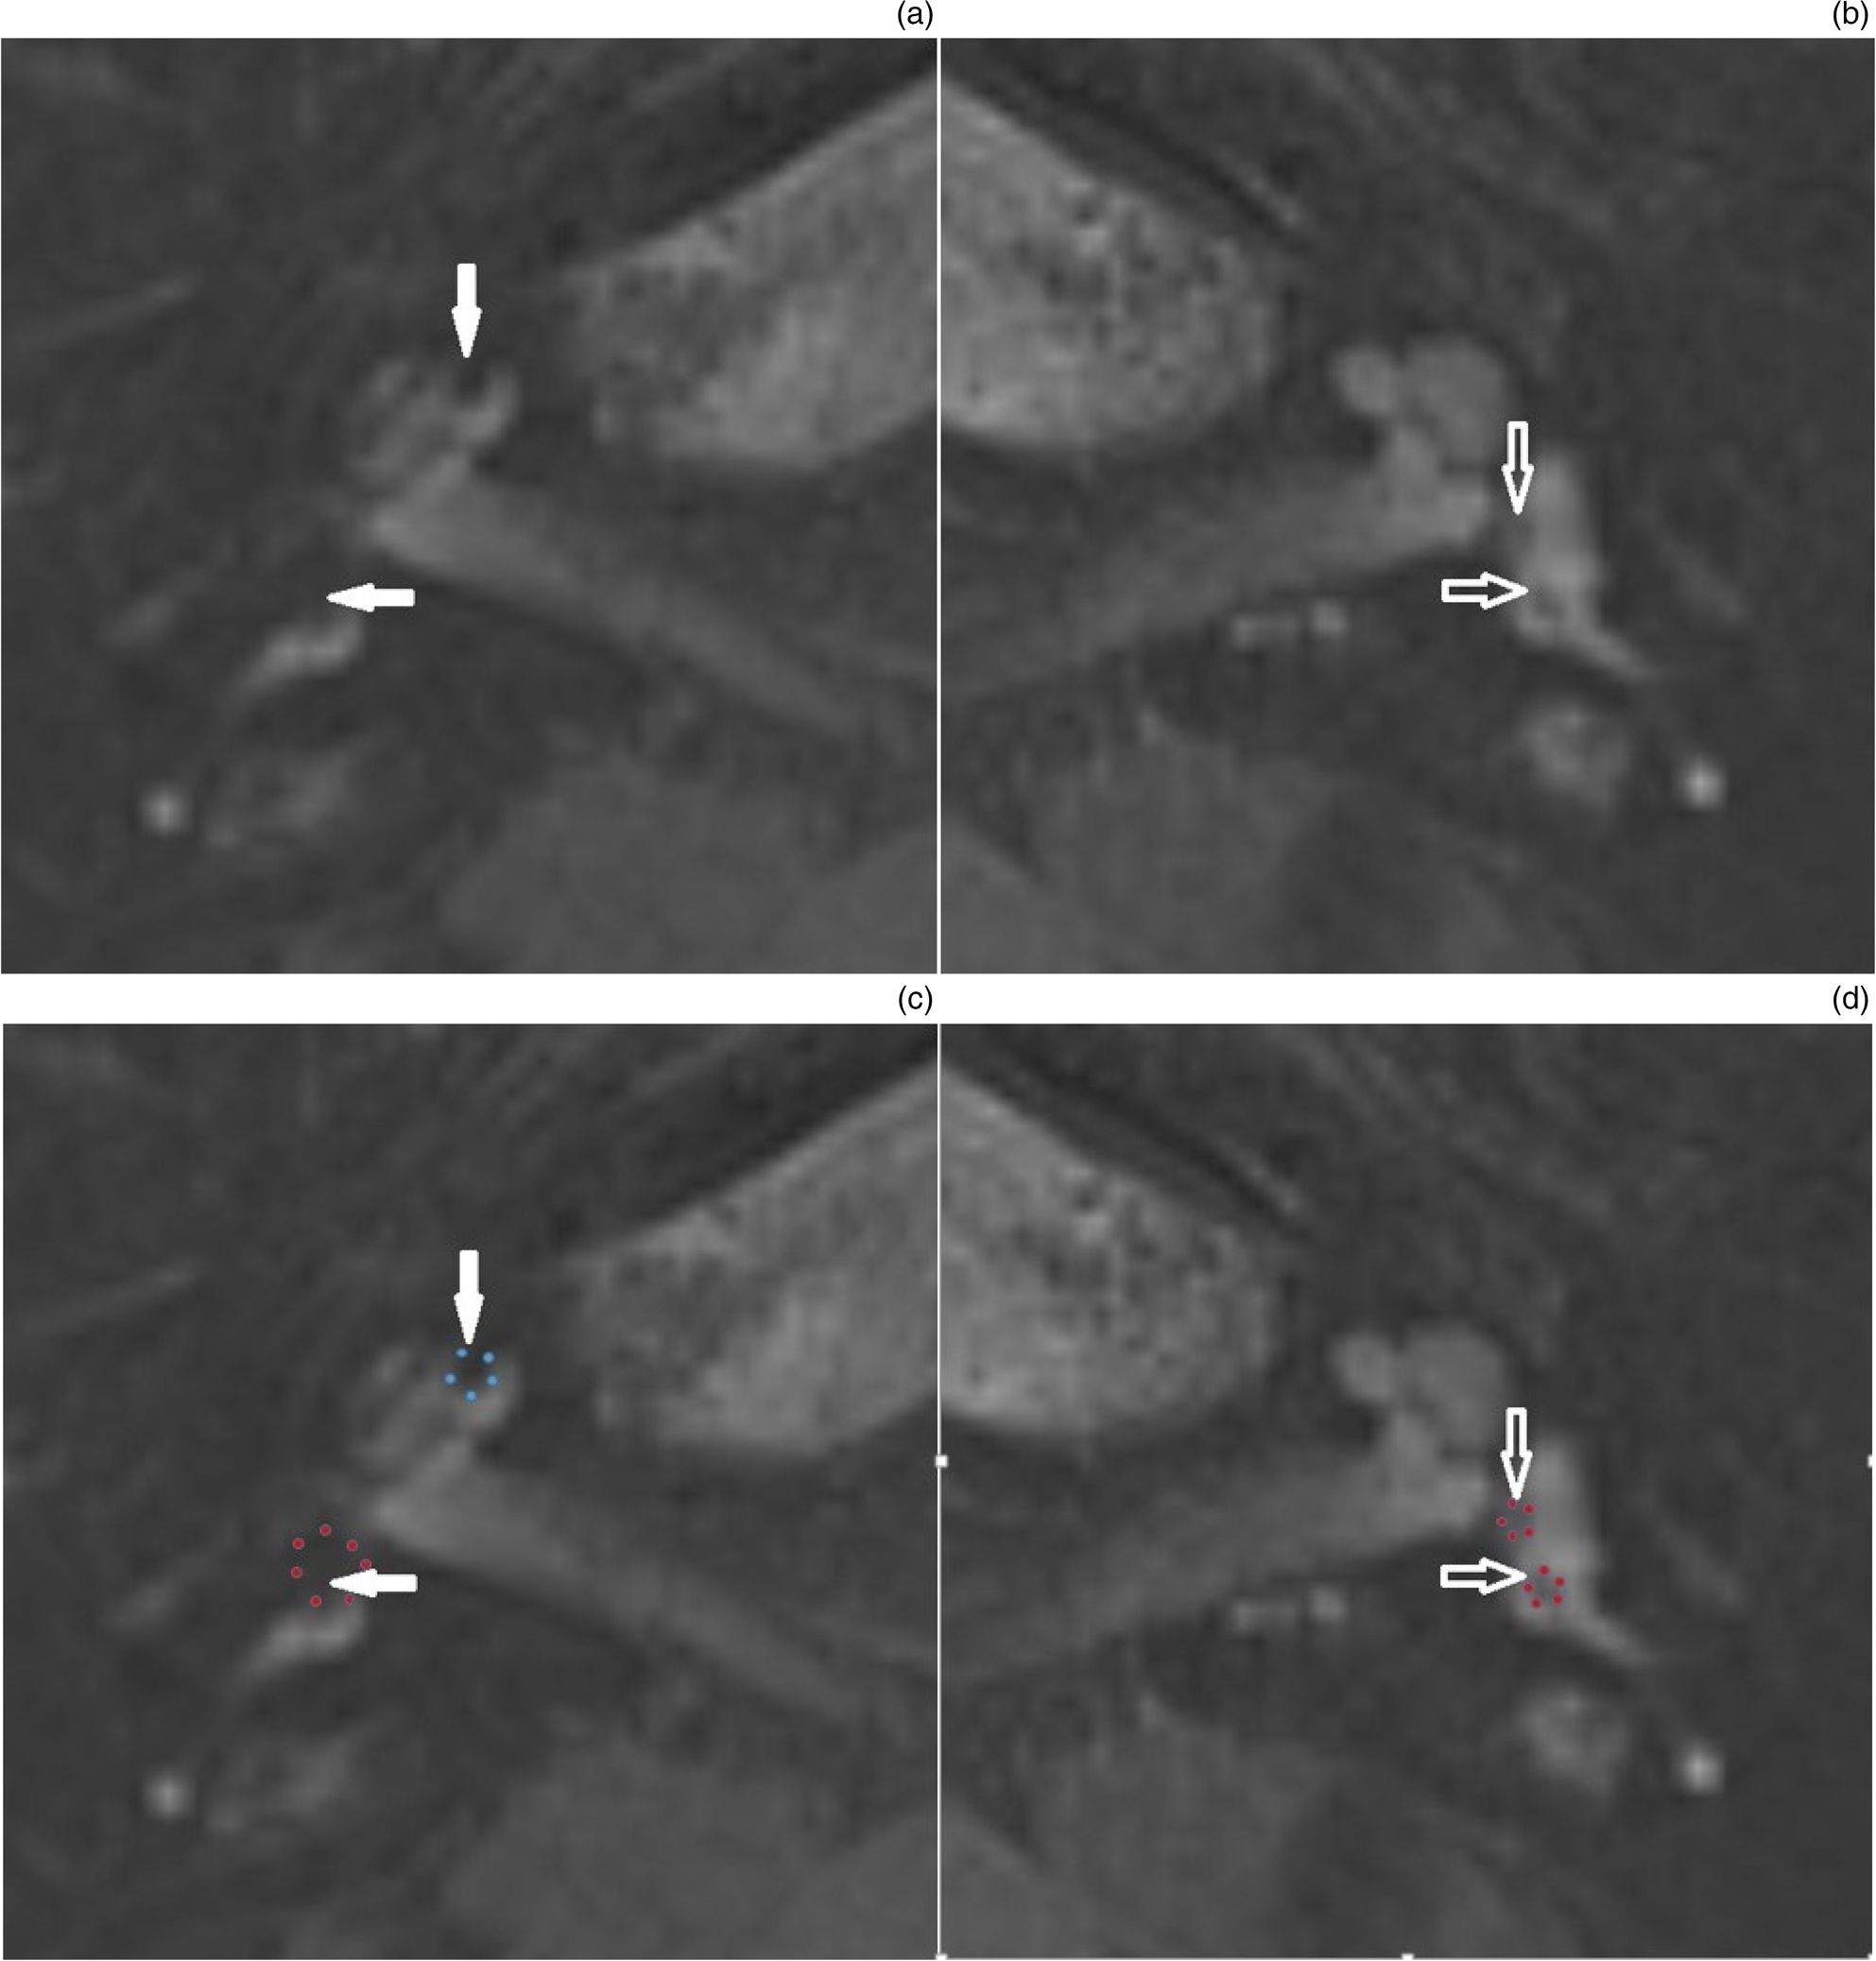

MRI of a patient with bilateral Meniere’s disease imaged using

MRI of a patient with bilateral Meniere’s disease imaged using Meniere's Disease Mri Scan Scans are a routine part of the investigation of many diseases. The study aimed to describe the methodology and detailed interpretation of magnetic resonance. ménière’s disease (md) is a chronic condition characterised by. this study aims to investigate the differences of imaging findings and features between md and other. at this writing (2022), it is clear that. Meniere's Disease Mri Scan.

MRI of a patient with bilateral Meniere’s disease imaged using Meniere's Disease Mri Scan Scans are a routine part of the investigation of many diseases. the vestibular aqueduct sign: ménière’s disease (md) is a chronic condition characterised by. at this writing (2022), it is clear that 3t mri can be used to identify hydrops, and might be useful in diagnosing meniere's disease. magnetic resonance imaging (mri) scan. Magnetic resonance imaging. Meniere's Disease Mri Scan.